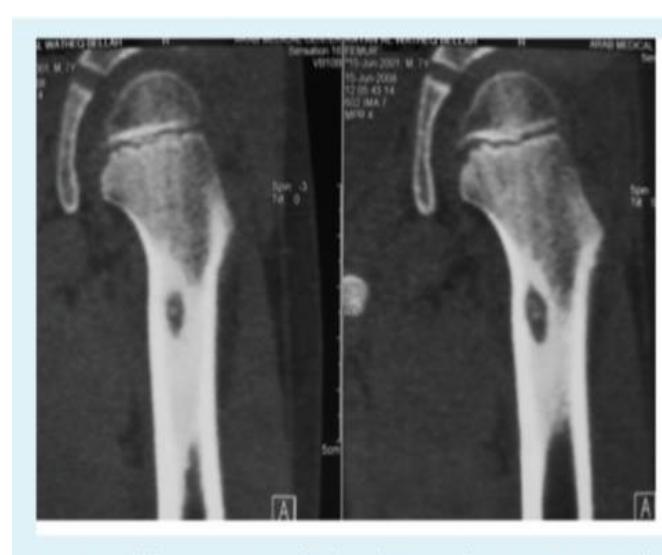

Bilateral Neck of Femur Fracture

Findings:

- Adult patient

- Osteoporotic bone changes

- Bilateral fracture neck of femur

Recommended additional imaging:

- CT scan for further evaluation